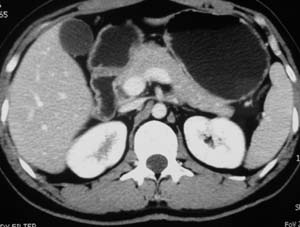

以下是引用子期在2010-3-19 20:47:00的发言:[br]血管畸形的ct增强应该有明显强化,本例并不相符合。本例双肾局部的略低密度影,累及肾盂,局部皮质明显变薄、内陷,增强扫描有轻度的强化,应考虑为炎性病变,患者为年轻男性,累及双肾的感染以结核较常见,可以没有明显的临床症状,尿中有时候也并不能查出什么;肾脓肿常有明显感染中毒症状,本例不符,另外一般的肾盂肾炎或肾小球肾炎通过小便就可确诊,其它还不能排除的是黄色肉芽肿性肾盂肾炎,然而单凭ct一般也很难鉴别。